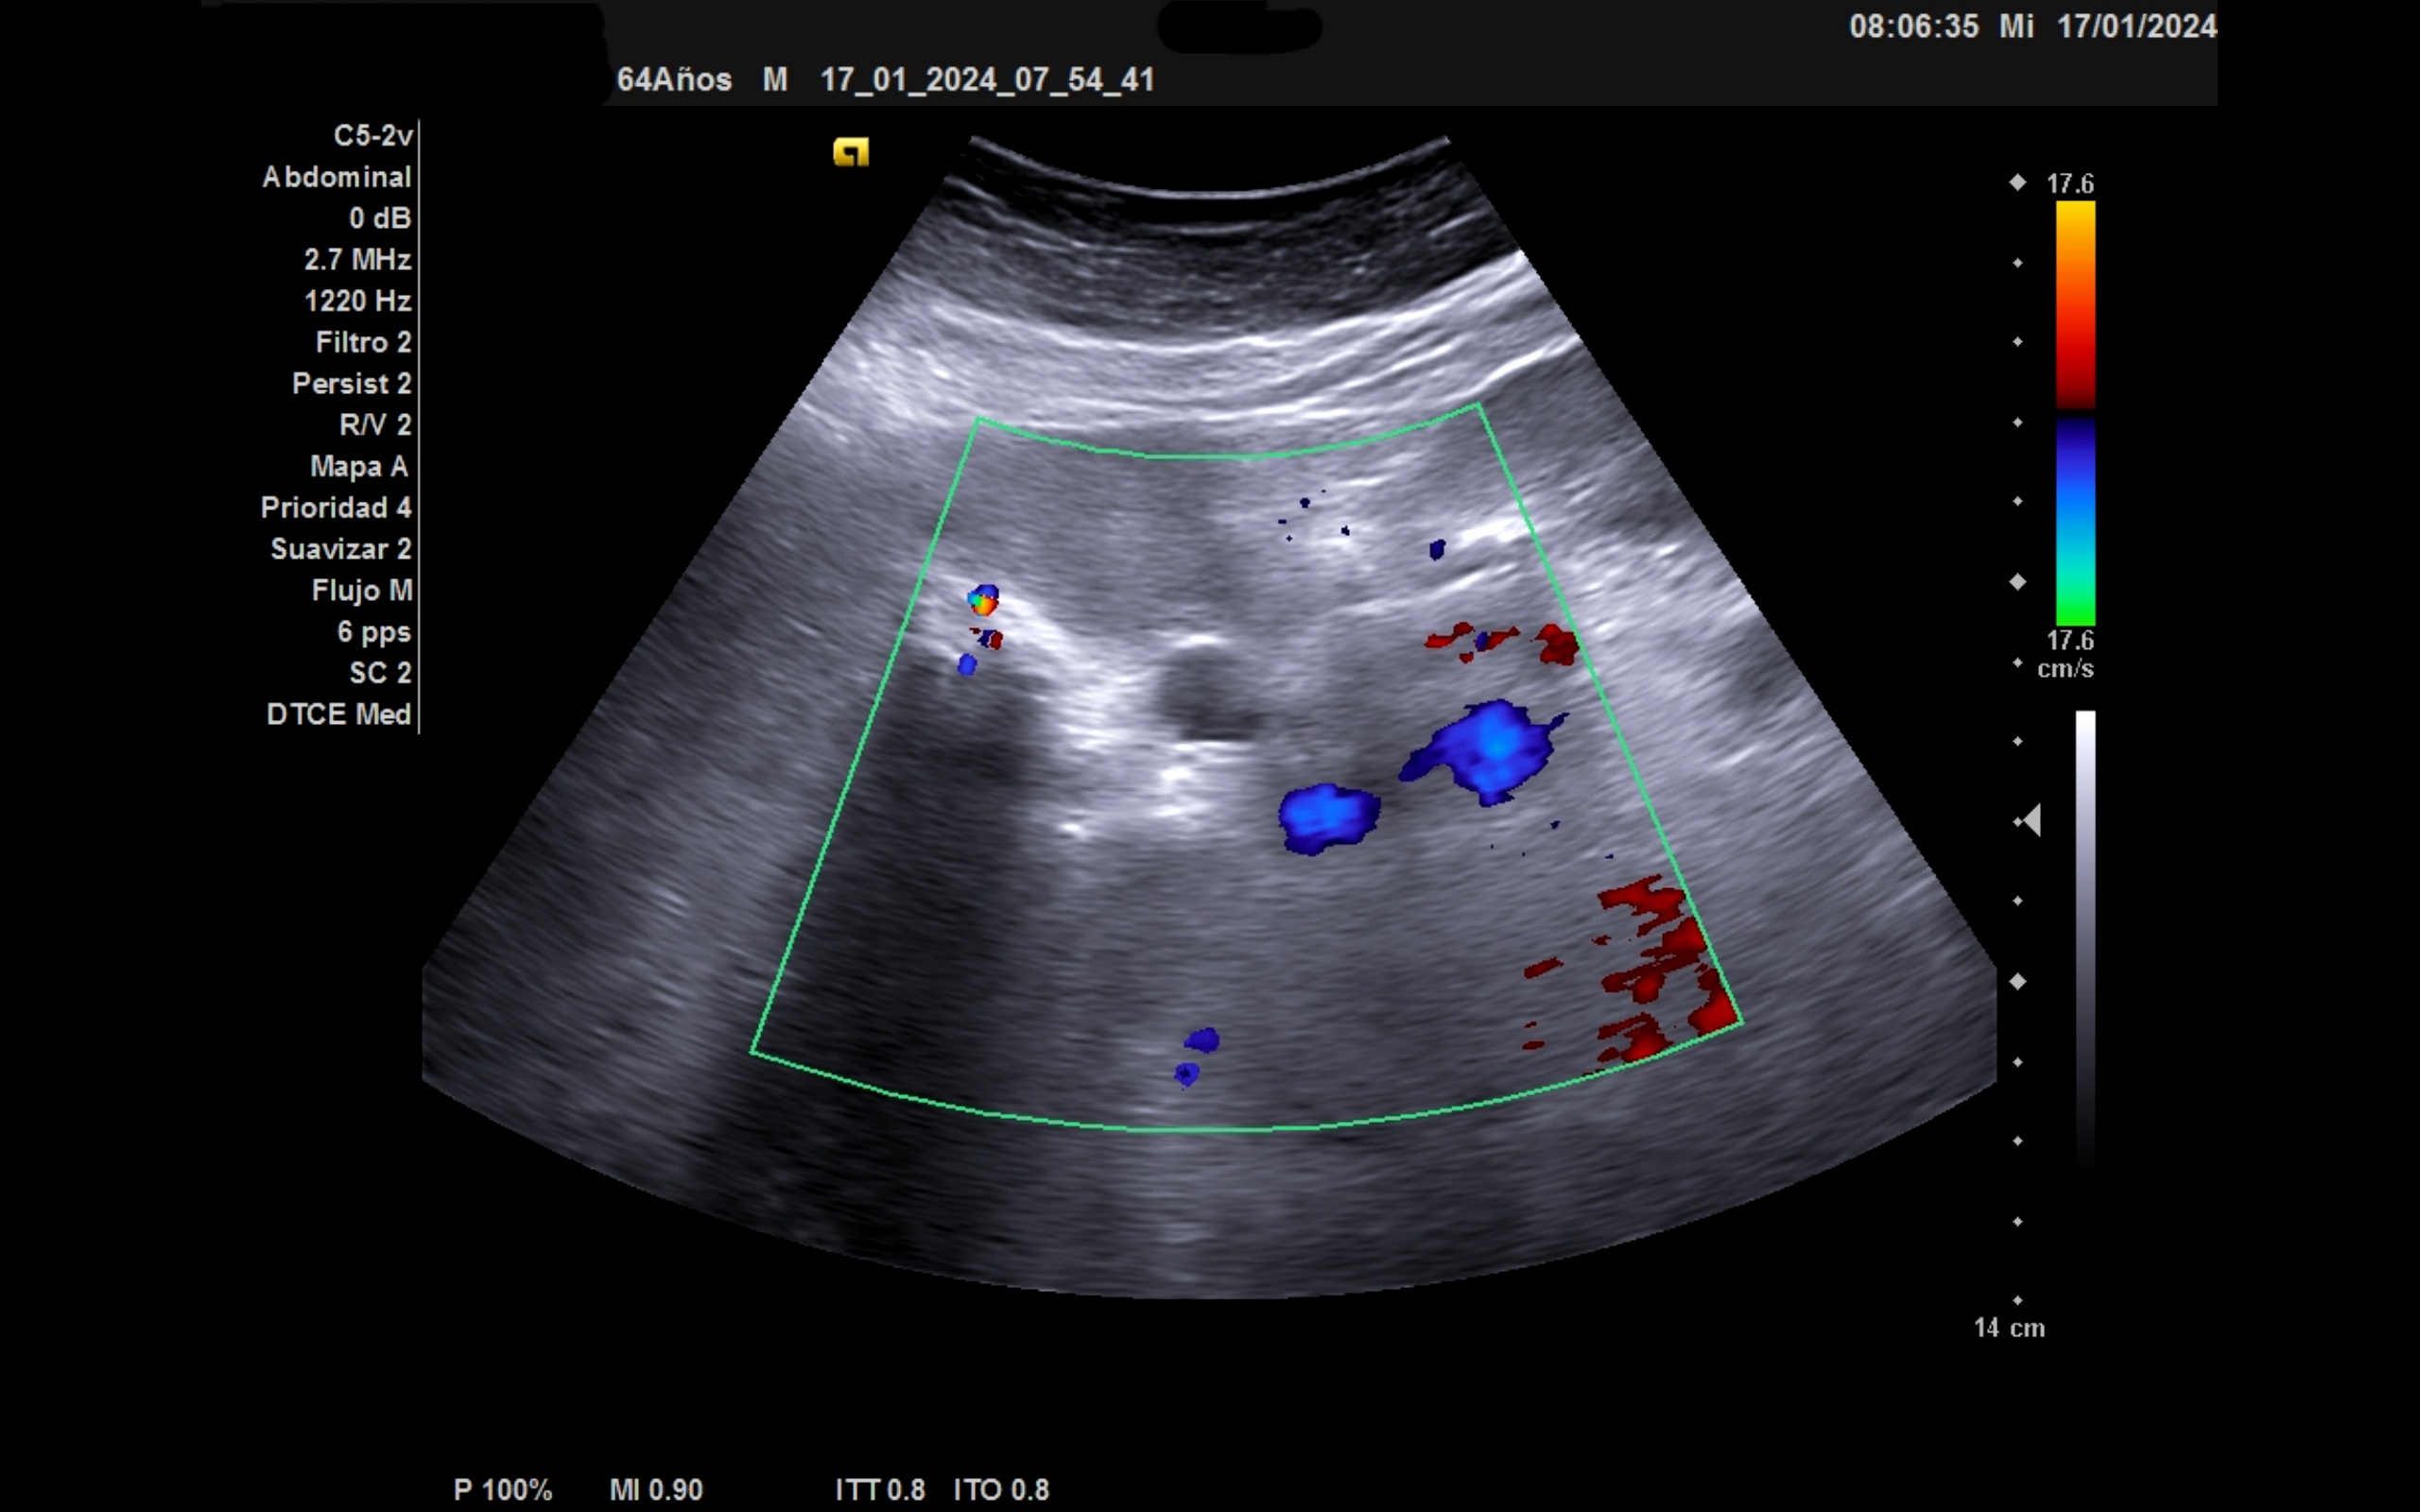

Ecografía clínica: Ventana subóptima. Parenquima hepático homogéneo con atenuación posterior, ángulo lóbulo hepático derecho redondeado, no aprecio claramente vesic biliar por imagen hiperecogénica con sombra. Pancreas visible, imagen anecogénica de 15 mm circular que no capta. Imagen tubular anecogénica: coledoco 13 mm. No aprecio alteración renal. Vejiga de la orina no replecionada. Ilíaca bilateral de 13,7 mm. Aorta de calibre normal.

Ictericia con Colelitiasis Múltiple con Dilatación de la via biliar con Stop ecográfico a nivel de pancreas.

La detección de la dilatación de la via biliar dilatada en paciente con hábito enólico nos hace sospechar la etiología maligna. Debe valorarse tanto parénquima hepático como pancreático, bazo y retroperitoneo.